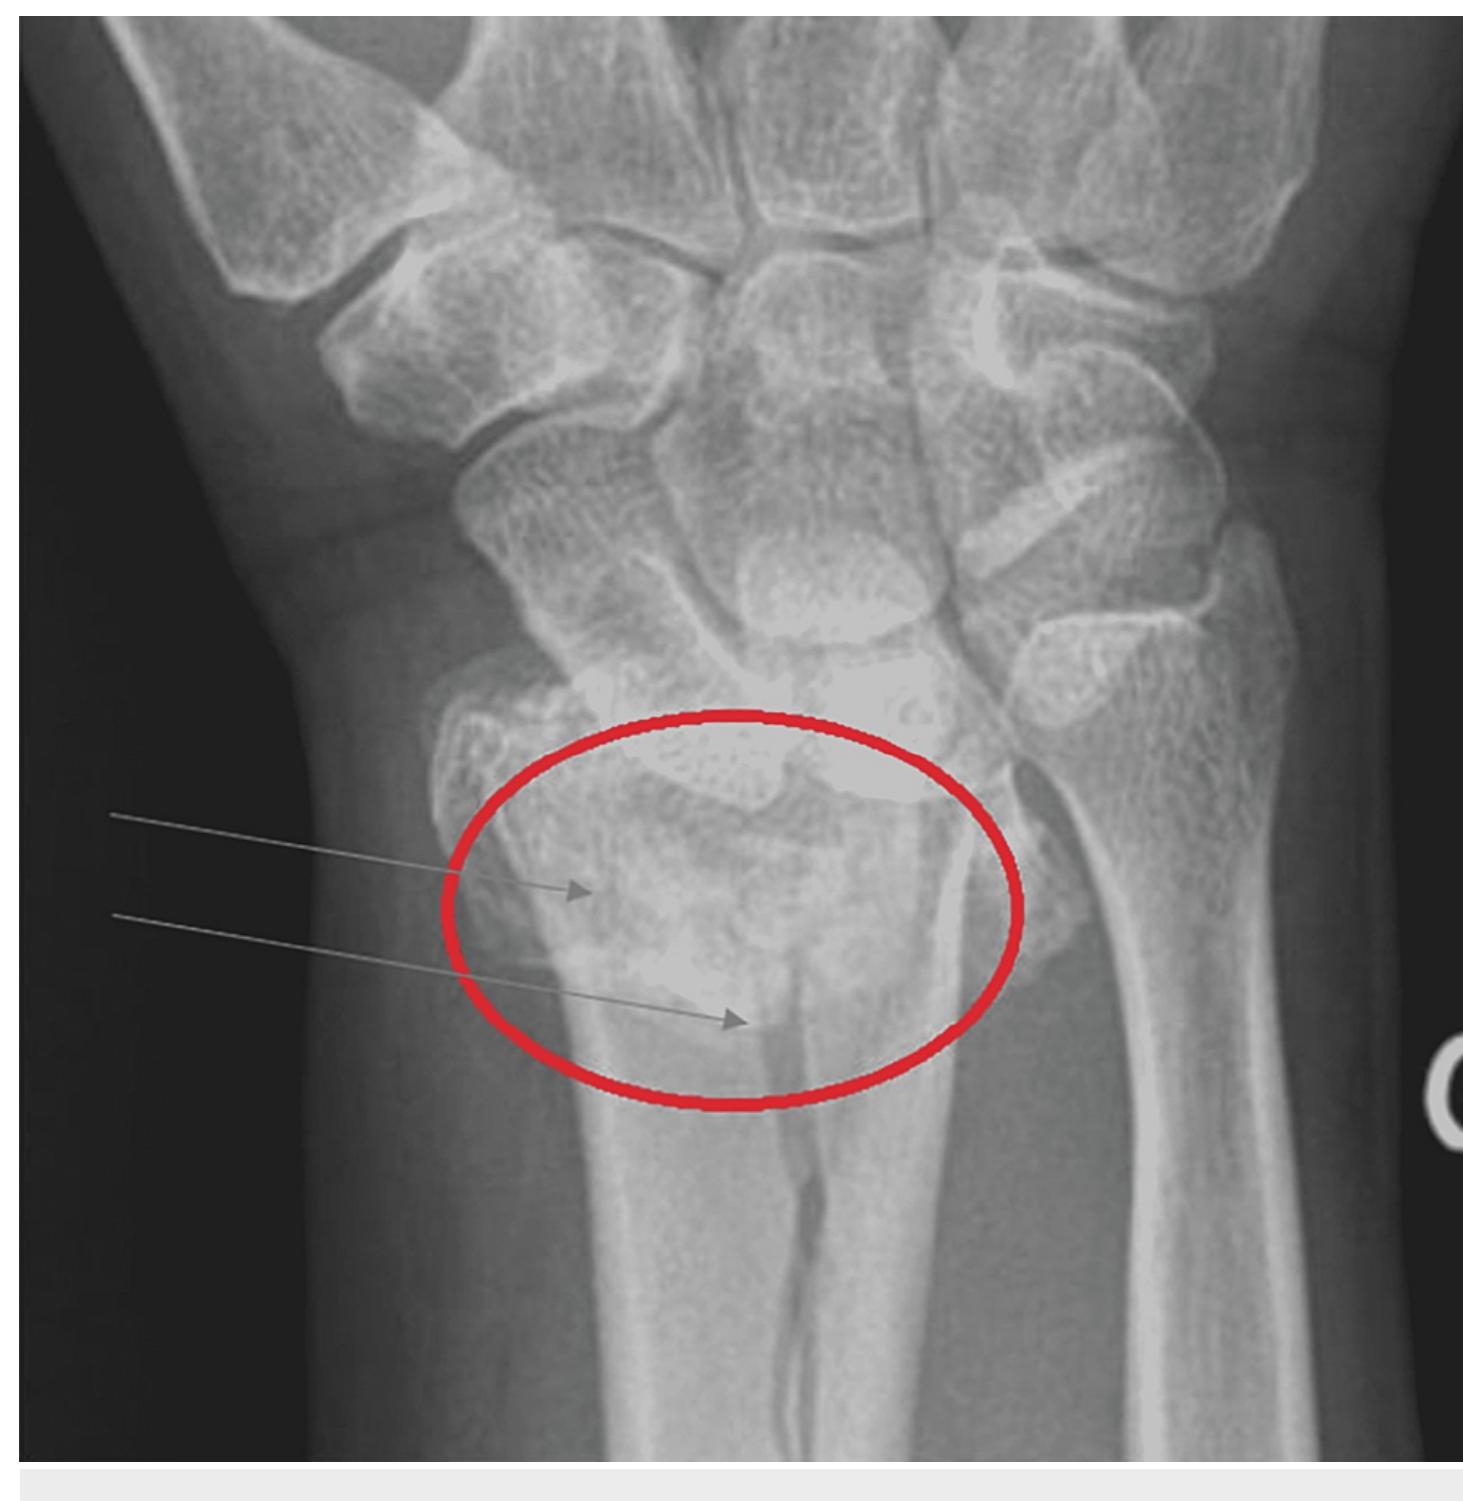

Colle Fracture Distal Radial Fracture Radiology Case Radiogyan Colle fracture is characterized as an extra articular fracture of the radial metaphysis caused by a fall on an outstretched hand (foosh), typically pronated forearm in wrist extension) causing dorsal angulation of the distal fracture fragment. Measurement of different angles and lines in assessment of distal radial fractures (see text).

Colle Fracture Distal Radial Fracture Radiology Case Gain clinical insights from the colles' fracture radiology case, featuring detailed analysis and x ray images. Case discussion appearances of colles fracture of the left distal radius associated with ulnar styloid fracture. it is the most common distal radial fracture in adults and seen more frequently with advancing age and in women with osteoporosis. Distal radius fractures are some of the most common fractures of the skeleton. many eponyms are used to describe common patterns of these fractures. one of these eponyms is the colles fracture, which describes an extra articular distal metaphyseal fracture of the radius with dorsal displacement. Colles fracture (distal radius) after foosh: key imaging findings dorsal angulation, ulnar styloid fracture. ct evaluates articular step off; orif for unstable displacement.

Colle Fracture Distal Radial Fracture Radiology Case Radiogyan Distal radius fractures are some of the most common fractures of the skeleton. many eponyms are used to describe common patterns of these fractures. one of these eponyms is the colles fracture, which describes an extra articular distal metaphyseal fracture of the radius with dorsal displacement. Colles fracture (distal radius) after foosh: key imaging findings dorsal angulation, ulnar styloid fracture. ct evaluates articular step off; orif for unstable displacement. Case discussion colles fracture of the left distal radius with concomitant fracture of the ulnar styloid process. notice the severe calcification of the radial and ulnar arteries. Colles fracture of the distal radial metaphysis. this case is used in 7 unlisted playlists. They consist of a fracture of the distal radial metaphyseal region with dorsal angulation and impaction, but without the involvement of the articular surface. this is the most common type of distal radius fracture. A colles' fracture is a fracture of the distal metaphysis of the radius with dorsal angulation and displacement leading to a 'silver fork deformity'. colles fractures are seen more frequently with advancing age and in women with osteoporosis.

Colle Fracture Distal Radial Fracture Radiology Case Case discussion colles fracture of the left distal radius with concomitant fracture of the ulnar styloid process. notice the severe calcification of the radial and ulnar arteries. Colles fracture of the distal radial metaphysis. this case is used in 7 unlisted playlists. They consist of a fracture of the distal radial metaphyseal region with dorsal angulation and impaction, but without the involvement of the articular surface. this is the most common type of distal radius fracture. A colles' fracture is a fracture of the distal metaphysis of the radius with dorsal angulation and displacement leading to a 'silver fork deformity'. colles fractures are seen more frequently with advancing age and in women with osteoporosis.